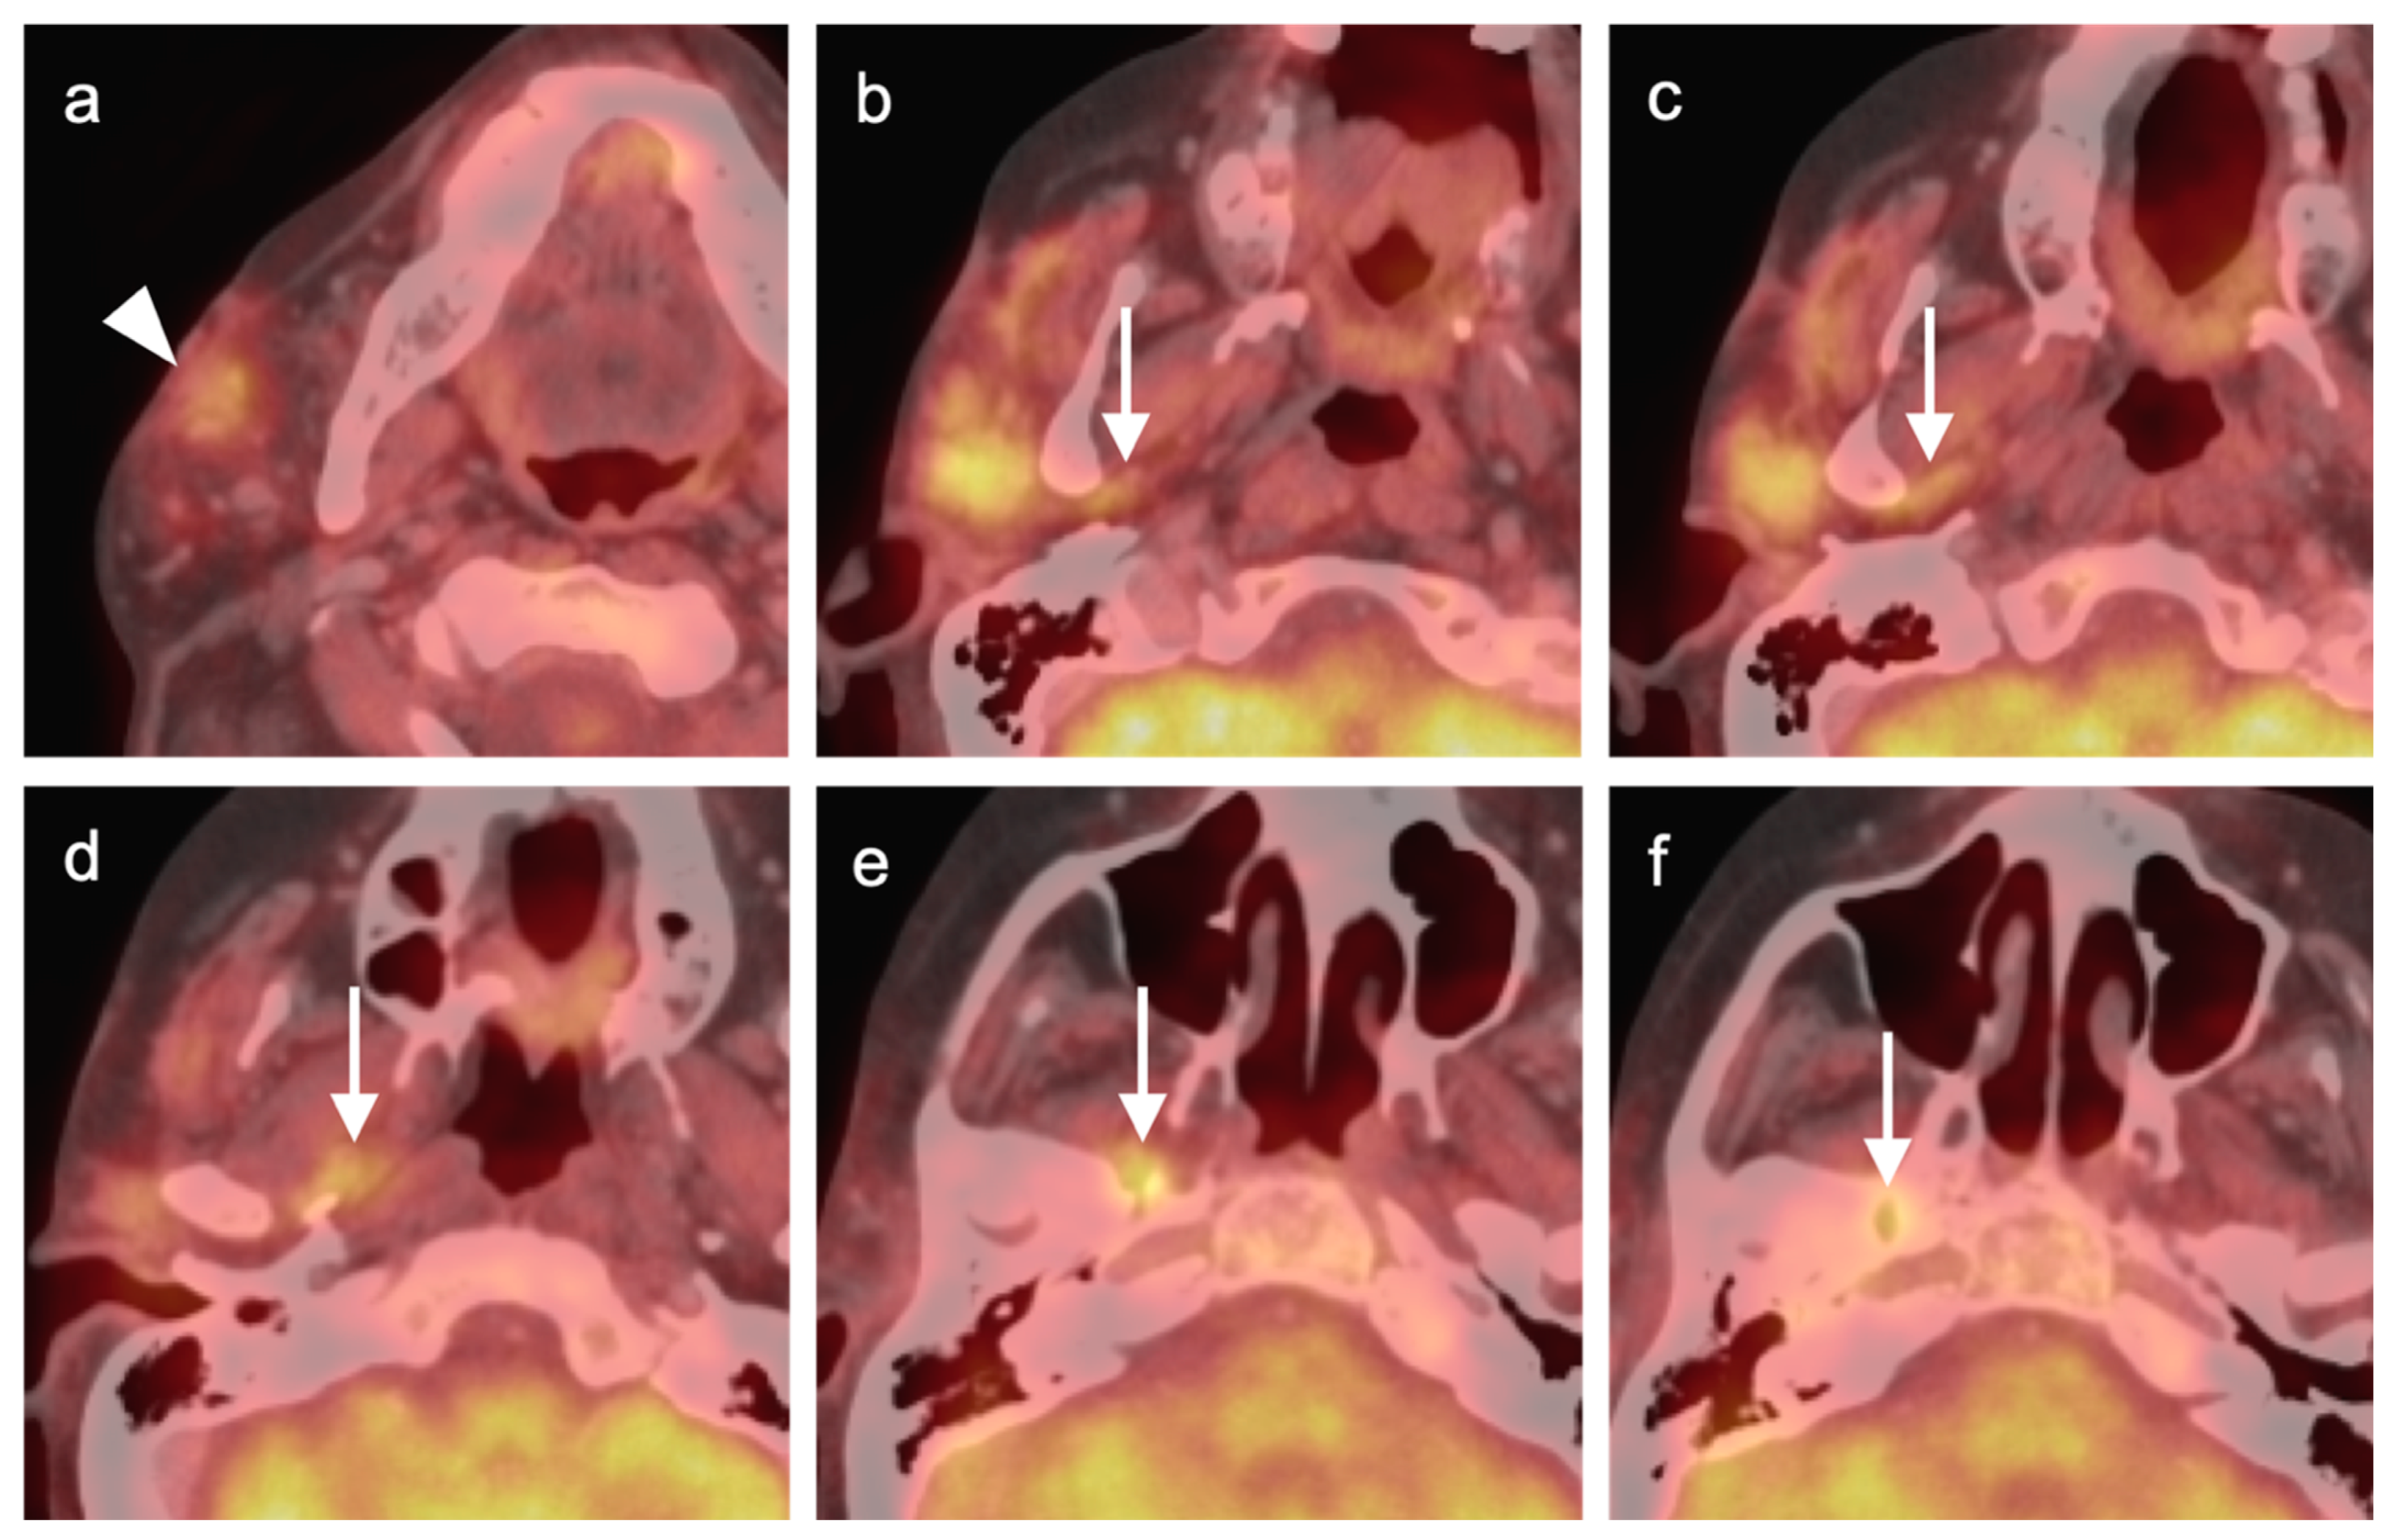

2.2. Squamous Cell Carcinoma of the Head and Neck (SCCHN)

2.3. Nasopharyngeal Carcinoma